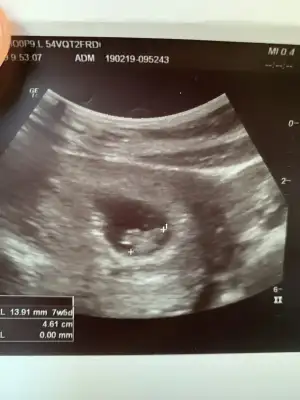

Ypk kuzum aynı foto işte. Karından. Arkadaş öyle diyince buraya da atayım dedim. Bildiğin solda bebek. Kızımın usg sine bakıyorum oda en sağa yapışık. Tam tersi tarafta. Senin usg yi atsana bi 7 haftalık olanı

Bak aynı doktor aynı makine bu da kızım 7+2 :) demek istediğim bu